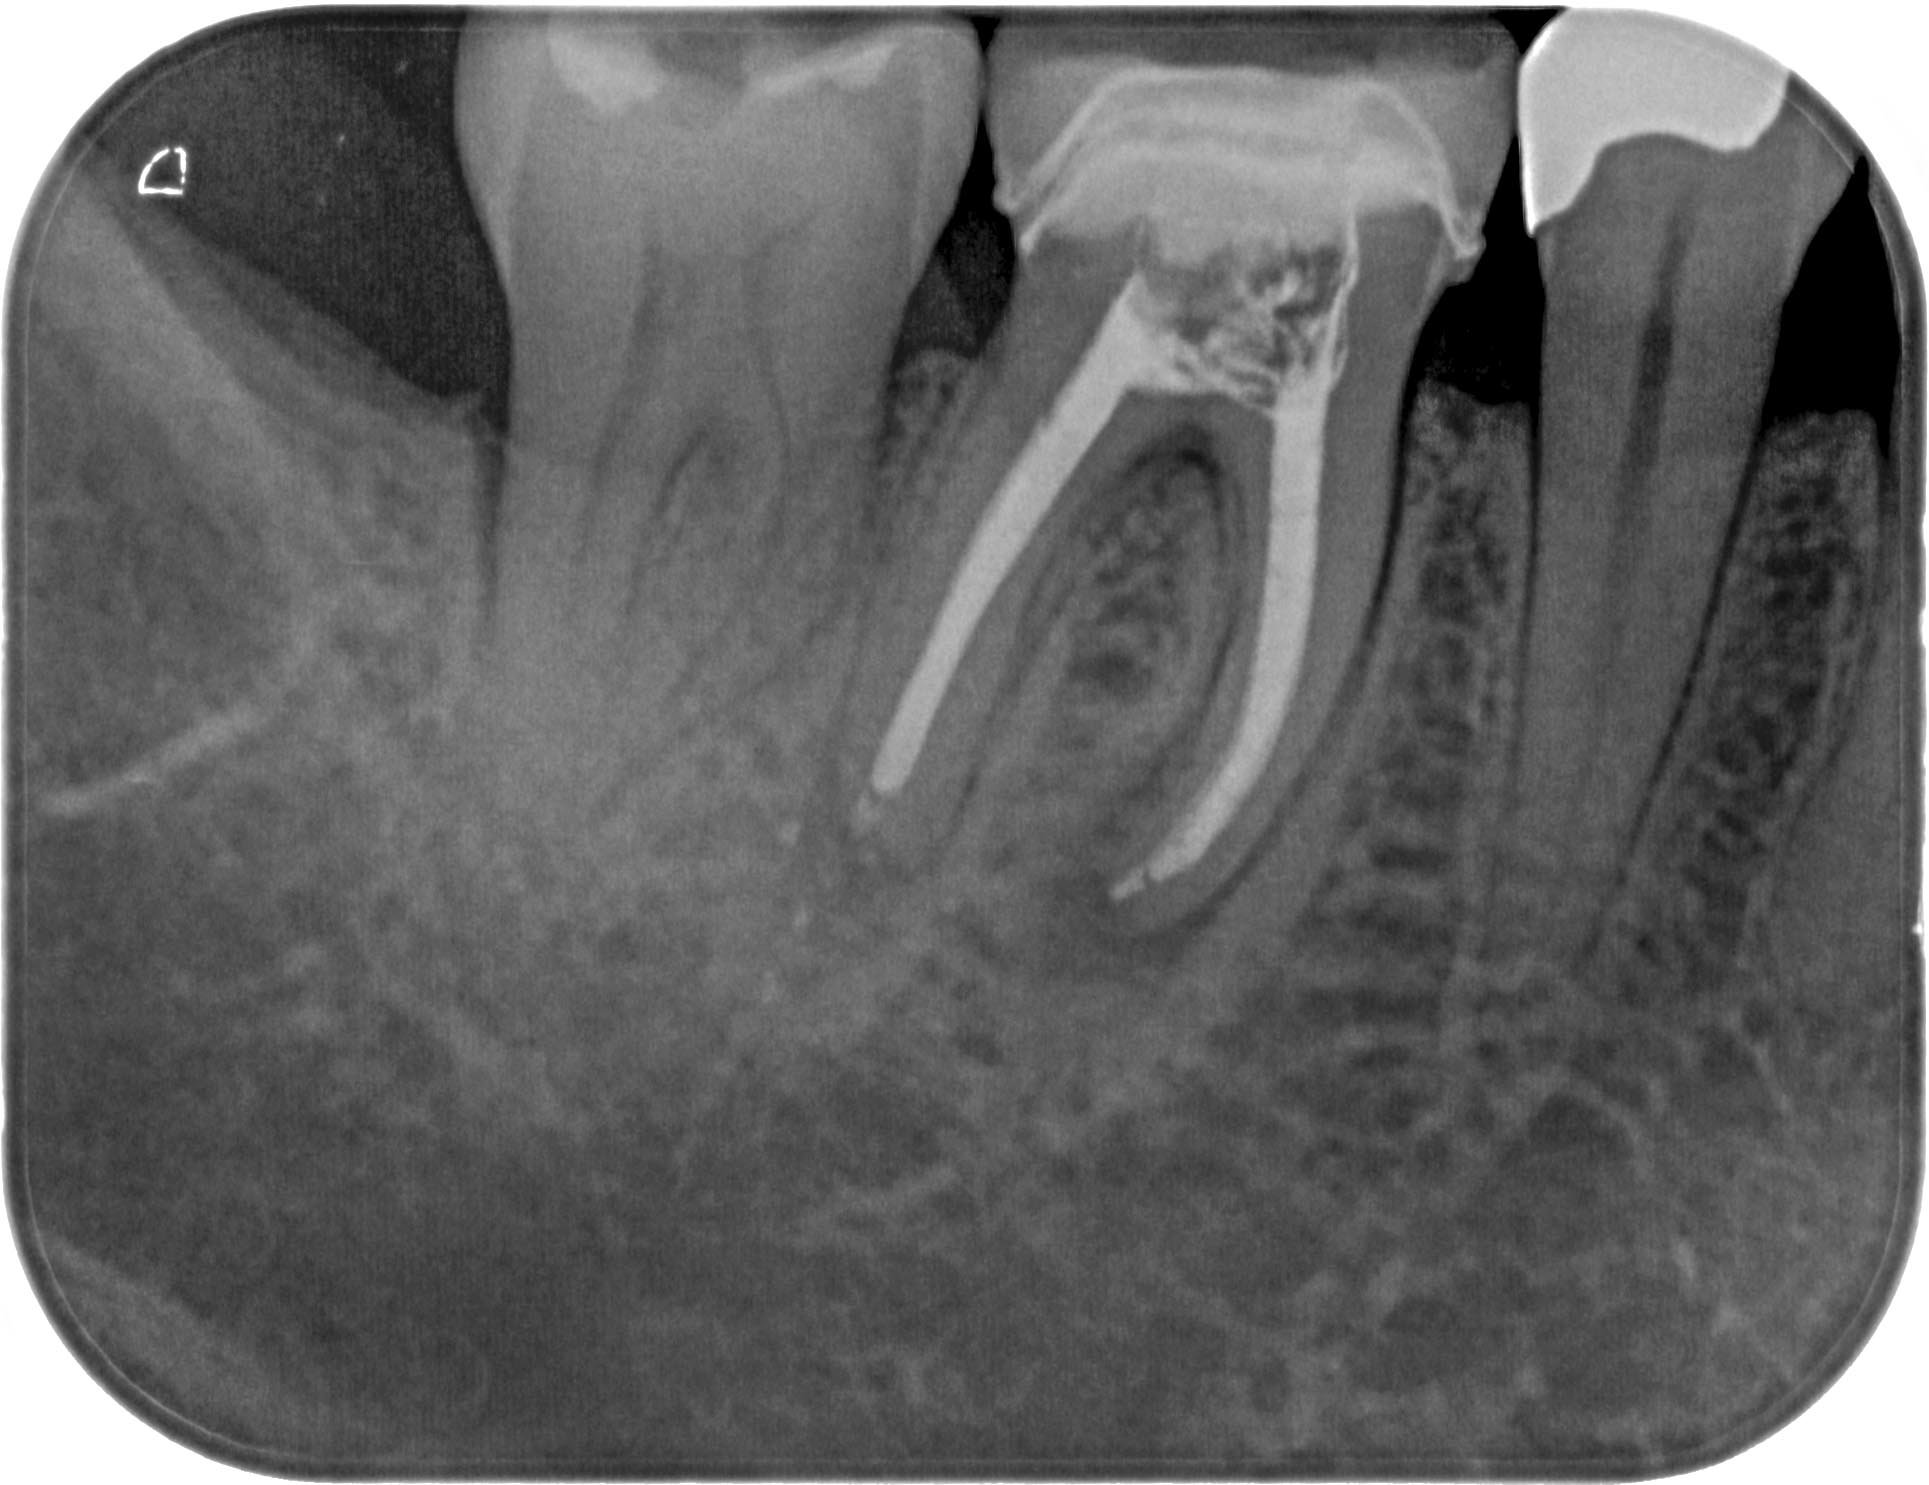

HS46 (1 von 1) Veröffentlicht 21. März 2016 am 1929 × 1485 in Calciumhydroxid- Überpressung (2) 21. März 2016